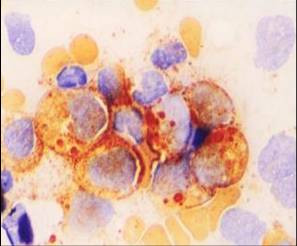

系統型脂膜炎細胞像實驗室檢查:

1.血常規、骨髓象及血沉 外周血象可見紅細胞、血小板減少。白細胞多數減少,可含有中毒顆粒,分類計數中性粒細胞減少,伴有核左移,但合併感染時白細胞增多,血沉增快。骨髓象可見粒細胞、紅細胞和巨核細胞不同程度的減少,有時粒細胞可含有少許中毒性顆粒,呈感染骨髓象。